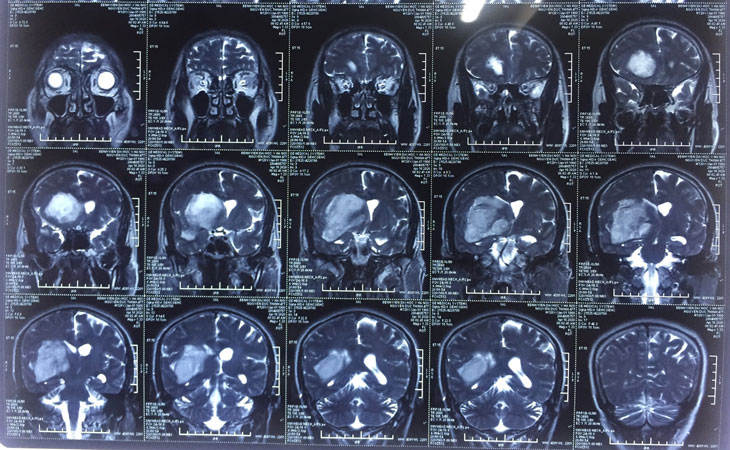

xuat-huyet-nao Phim CT-scan một trường hợp xuất huyết não